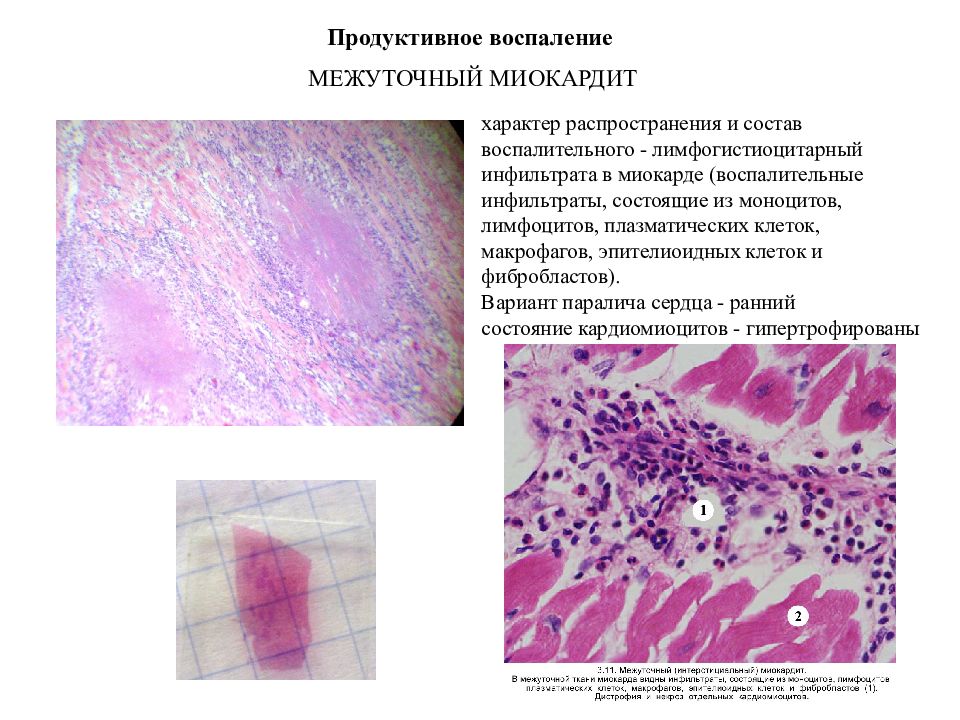

Межуточный миокардит: гистологические исследования

Раздел: Идеи и советы